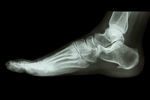

足底筋膜炎はどの様な痛みを引き起こしますか?

組織の炎症、癒着により、かかとやアーチ周辺に痛みを引き起こします。